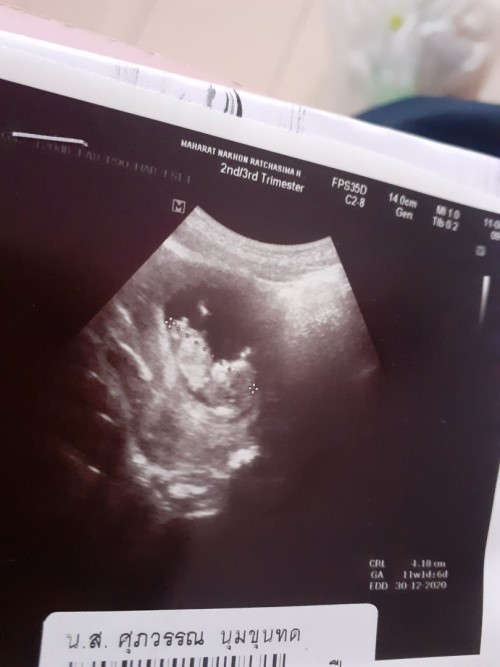

11w6วัน